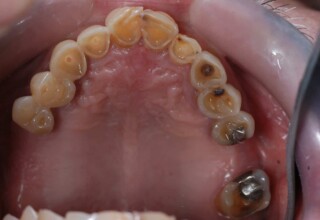

Εκτεταμένη αποκατάσταση με στεφάνες(θήκες) σχεδόν σε όλα τα δόντια λόγω εκτεταμένων αποτριβών, παλαιών αποκαταστάσεων, οπισθίων απονευρώσεων και αισθητικών προβλημάτων. Ο ασθενής(60 ετών) παρουσίαζε έντονο βρυγμό (τρίξιμο δοντιών) που δεν είχε αντιμετωπίσει ποτέ, με αποτέλεσμα μεγάλες αποτριβές που απειλούσαν την ακεραιότητα των οπισθίων δοντιών. Οι ανασυστάσεις(σφραγίσματα) των δοντιών έγιναν κυρίως με συγκολλούμενα ρητινώδη υλικά και τρεις χυτούς άξονες ψευδοκολοβώματα. Τοποθετήθηκαν προσωρινές στεφάνες όπου εκτιμήθηκε το επιθυμητό μέγεθος, το σχήμα και η θέση των δοντιών πριν κατασκευαστούν οι τελικές μόνιμες στεφάνες.